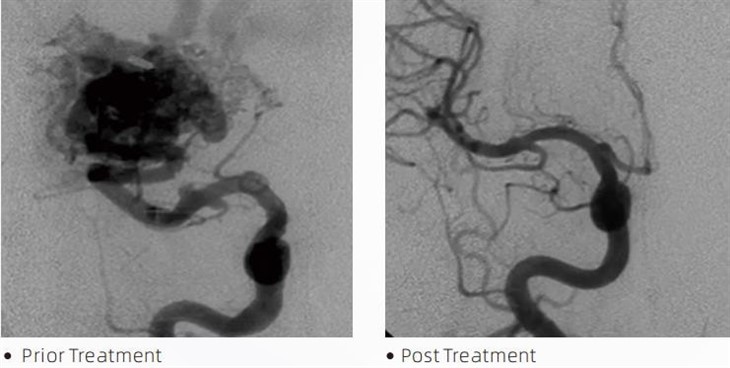

گدازهTmچسب آمبولیک یک وسیله پزشکی است که توسط متخصصان نورو رادیولوژی مداخله ای در طی روش های کم تهاجمی برای درمان بیماری هایی مانند آنوریسم های مغزی، ناهنجاری های شریانی وریدی و تومورها استفاده می شود. چسب آمبولیک لاوا مزایای متعددی را برای متخصصان پزشکی و بیماران از نظر ایمنی، سهولت استفاده و اثربخشی ارائه می دهد. گدازه قادر است رگ های خونی را به سرعت و کارآمد ببندد. این فرآیند شامل تزریق مستقیم چسب به داخل رگ مورد نظر است، جایی که پلیمریزه شده و به شکل یک توده گچ مانند که آنوریسم یا ناهنجاری را پر می کند، سخت می شود. سپس به طور موثر جریان خون ضایعه را قطع می کند و از پارگی آن جلوگیری می کند و خطر آسیب دائمی یا سکته مغزی را کاهش می دهد. گدازه شامل Lava-12، Lava-18 و Lava-34 است. هر فرمول برای رفع نیازهای بالینی خاص طراحی شده است. Lava-18 فرمول استاندارد برای استفاده عمومی است. Lava{5}} چسبی با ویسکوزیته بالا برای مخازن با جریان بالا است. در حالی که گدازه{7}} ویسکوزیته کمتری دارد و جریان پذیری بیشتری دارد و اجازه میدهد تا رگهای ریز دیستال ایجاد شوند. با این گزینهها، نورو رادیولوژیستهای مداخلهای میتوانند فرمولهای گدازه مناسب را برای اطمینان از نتایج بهینه انتخاب کنند. یکی از قابل توجه ترین ویژگی های گدازه، عدم چسبندگی آن است. این ماده به طور ویژه فرموله شده است تا تا رسیدن به منطقه مورد نظر پایدار بماند. این ویژگی به این معنی است که چسب آمبولیک لاوا می تواند به طور دقیق در داخل شریان قرار گیرد و بدون چسبیدن یا چسبیدن به بافت اطراف در آنجا باقی بماند.